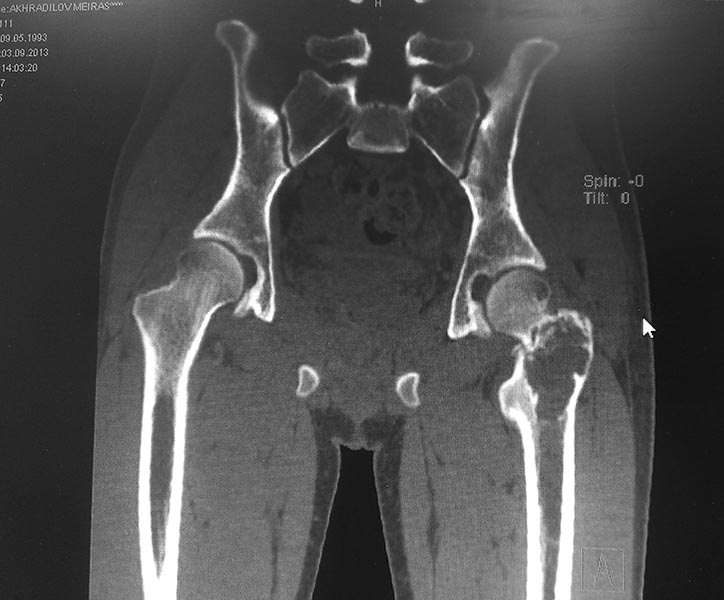

кисте. Пациенту произведено КТ обеих тазобедренных суставов.

Заключение: КТ - признаки объемного образования области шейки и большого

вертела левой бедренной кости дифференцировать с фиброзной дисплазией.

Сростающийся патологический чрезвертельный перелом левой бедренной кости.